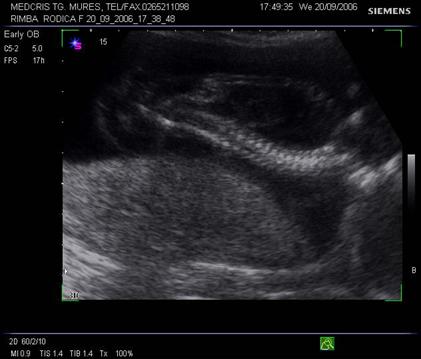

Fig. nr. 242. Aceeati sarcina ca in figura precedenta, se remarca lichidul pericardic si bilateral cel pleural, in sectiune transversala la nivel toracic fetal.